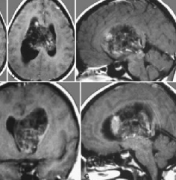

磁共振成像对顶盖肿瘤的显示比CT更可靠,应该在每个患有脑积水的儿童和青少年中进行排序。磁共振成像能够可靠地检测到顶盖肿块,是一种可靠的随访成像方式。对于肿瘤区域对比...

中脑肿瘤的手术入路解读